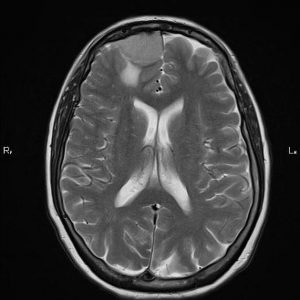

Cavernoma

Lượt xem: 237» 19-06-2020 -